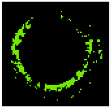

Regarding Figure 9, FCMPSO-mED achieved a greater SW than HFCM-mED for Patients 3 and 4, while HFCM-mED achieved better results for Patients 2 and 6. The two methods obtained the same results for the other patients. Figure 10 illustrates the comparison of SW achieved by the FCMPSO-mED, KMPSO-mED, and HFCM-kNN models.

Figure 10.

Comparison of the FCMPSO-mED, KMPSO-mED, and HFCM-kNN models.

Based on this figure, the FCMPSO-mED and KMPSO-mED models achieve higher SW values rather than the HFCM-kNN model. The experimental results suggest that the mED method has the potential for significant benefits in practice. In terms of memory consumption, this method requires the storage of only the colour-based feature matrix.